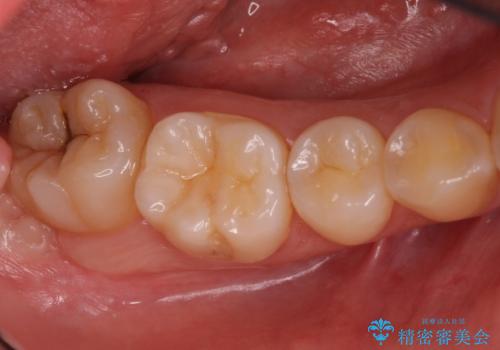

奥歯の黒ずみが気になる セラミックインレーでの治療

- 奥歯の黒ずみが気になるとのことで来院されました。

樹脂での治療も考えましたが、材料の劣化を避けるためにセラミックインレーでの治療をすることとなりました。

- 右下7 セラミックインレー 77,000円費用は治療当時の料金となります